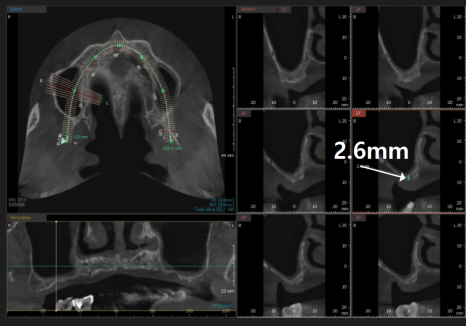

CT로 찾아낸 최적의 위치

뼈가 없어서 안 된다구요? 70대 당뇨 무치악 환자분의 전체 임플란트 사례

전체적으로 뼈가 얇았기에,

CT 정밀 분석을 통해

그나마 뼈 상태가 양호한 부위를

전략적으로 선택했습니다.

250310

총 6개의 임플란트를 심고

보철로 연결해 12개의 치아를

만드는 계획을 세웠죠.

또한 당뇨 수치와 연령을 고려해

오른쪽, 왼쪽, 앞니 세 번으로

나누어 진행했습니다.